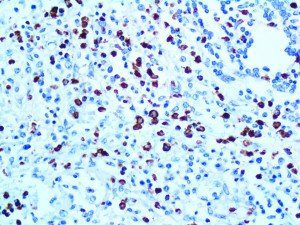

It is the ICU physician who is most likely to witness one of the deadliest manifestations of the abnormal immunological response, the cytokine storm syndrome (CSS). This response is also referred to by some as the cytokine release syndrome (CRS). CSS is characterized by continuous activation and expansion of macrophage and lymphocyte populations, which secrete large amounts of cytokines, causing the cytokine storm. This massive cytokine release is akin to hemophagocytic lymphohistiocytosis (HLH) disease, a syndrome characterized by initial unchecked and persistent activation of cytotoxic T lymphocytes and NK cells.

Clinical and laboratory manifestations of HLH include fever, enlarged liver and/or spleen, neurologic dysfunction, coagulopathy, liver dysfunction, cytopenias (i.e., low levels of erythrocytes, leukocytes, and/or platelets), hypertriglyceridemia, hyperferritinemia, hemophagocytosis, and eventually diminished NK cell activity as the immune system becomes progressively paralyzed. HLH can be familial (primary HLH) or secondary to another disease process (sHLH), such as rheumatic disease, in which it is referred to as macrophage activation syndrome (MAS, characterized by elevated ferritin).